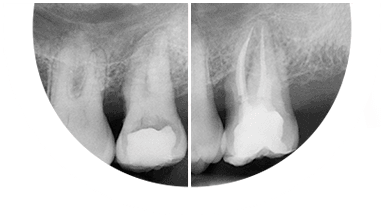

Paciente de 76 anos do sexo masculino

Motivo da consulta: Paciente desdentado total, procurava colocar dentes.